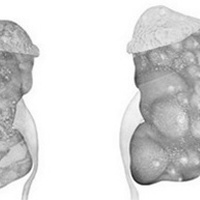

Инфекции мочевыводящих путей – состояние инфицирования мочевыводящего тракта микрофлорой, которая вызывает его воспаление.Различают инфекцию верхних (пиелонефрит) и нижних мочевых путей (цистит, простатит, уретрит) по наличию или отсутствию симптомов (симптоматическую или бессимптомную бак-териурию), по происхождению инфекции (внебольничную или нозокомиальную), осложненные и неосложненные.

Осложненные инфекции сопровождаются функциональными или анатомическими аномалиями верхних или нижних мочевых путей.